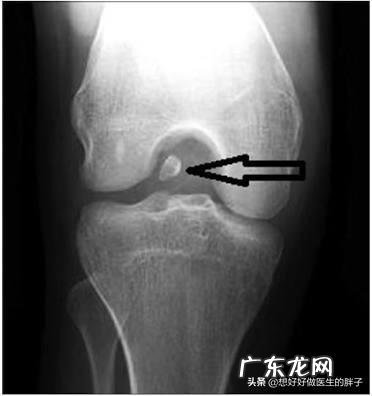

diyi,半月板撕裂 。我们膝关节内有两块非常重要的软骨,因为形状像月牙,所以称之为半月板 。半月板其实就是两块比较大的软骨,在关节的屈伸活动当中,它的形态是动态变化的,会有厚薄的变化以及宽窄的变化,这样才能更好的缓冲关节在运动当中承受的压力,匹配关节的形状,使关节能够做正常的屈伸运动 。